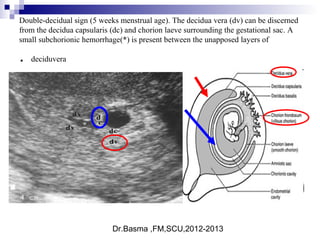

Double-decidual sign (5 weeks menstrual age). The decidua vera (dv) can be discerned

from the decidua capsularis (dc) and chorion laeve surrounding the gestational sac. A

small subchorionic hemorrhage(*) is present between the unapposed layers of

deciduvera.

 The "Double Decidual

Sign"consists of two

echogenic rings

surrounding the

hypoechoic gestational

sac.

 The inner ring represents

the chorion, embryonic

disc and decidua

capsularis (*). The outer

ring represents the

decidua parietalis (**).